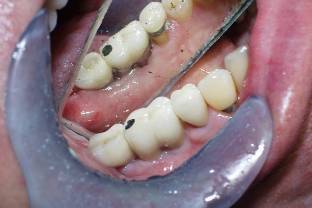

Replace Two Lower molars (Three Implants Two Teeth)

Mirror reflection

-Implant

Dental Implant